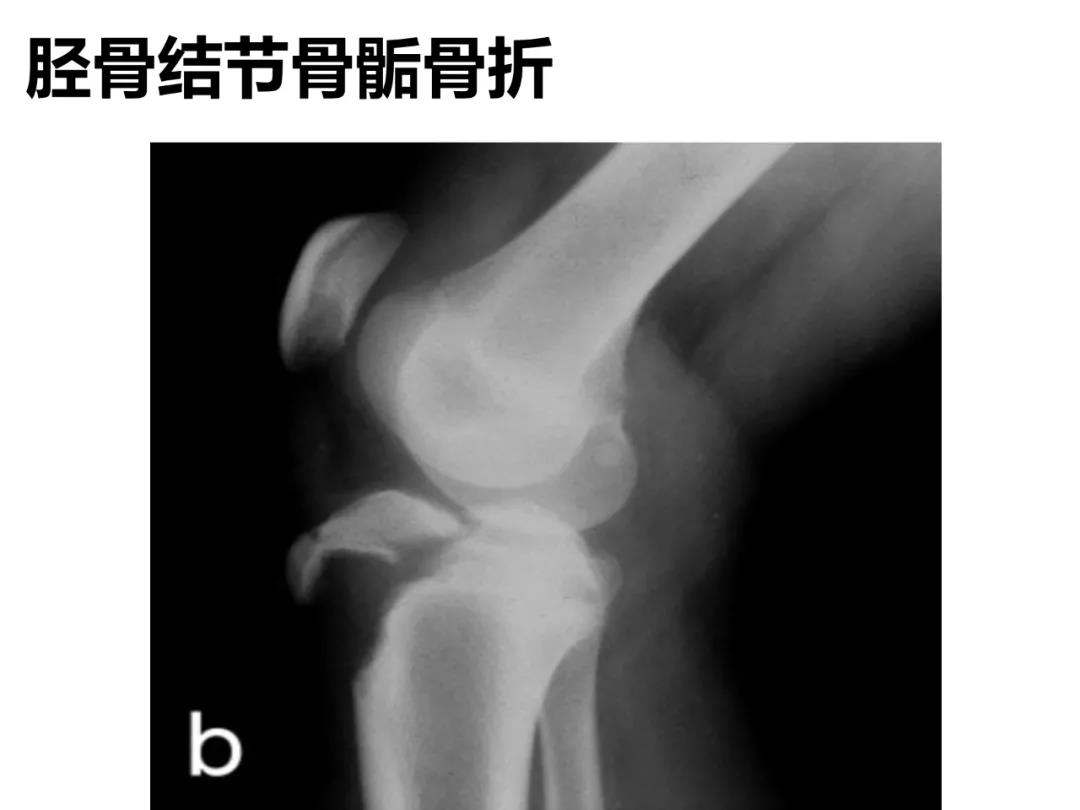

小儿骨科X线片汇总,临床读片宝典!